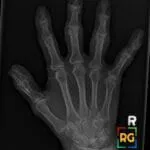

- Radiology Cases: Images with a to-the-point discussion highlighting the specific diagnostic criteria.

- Radiology Spotters: 700+ spot / “Aunt-Minnie” cases divided into sets of 10 each!

Latest Radiology Cases